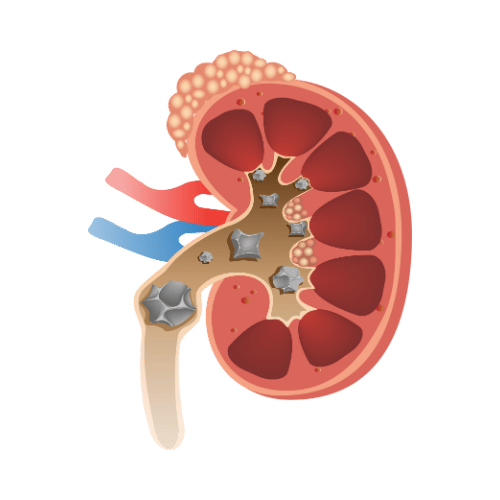

Kidney Stone